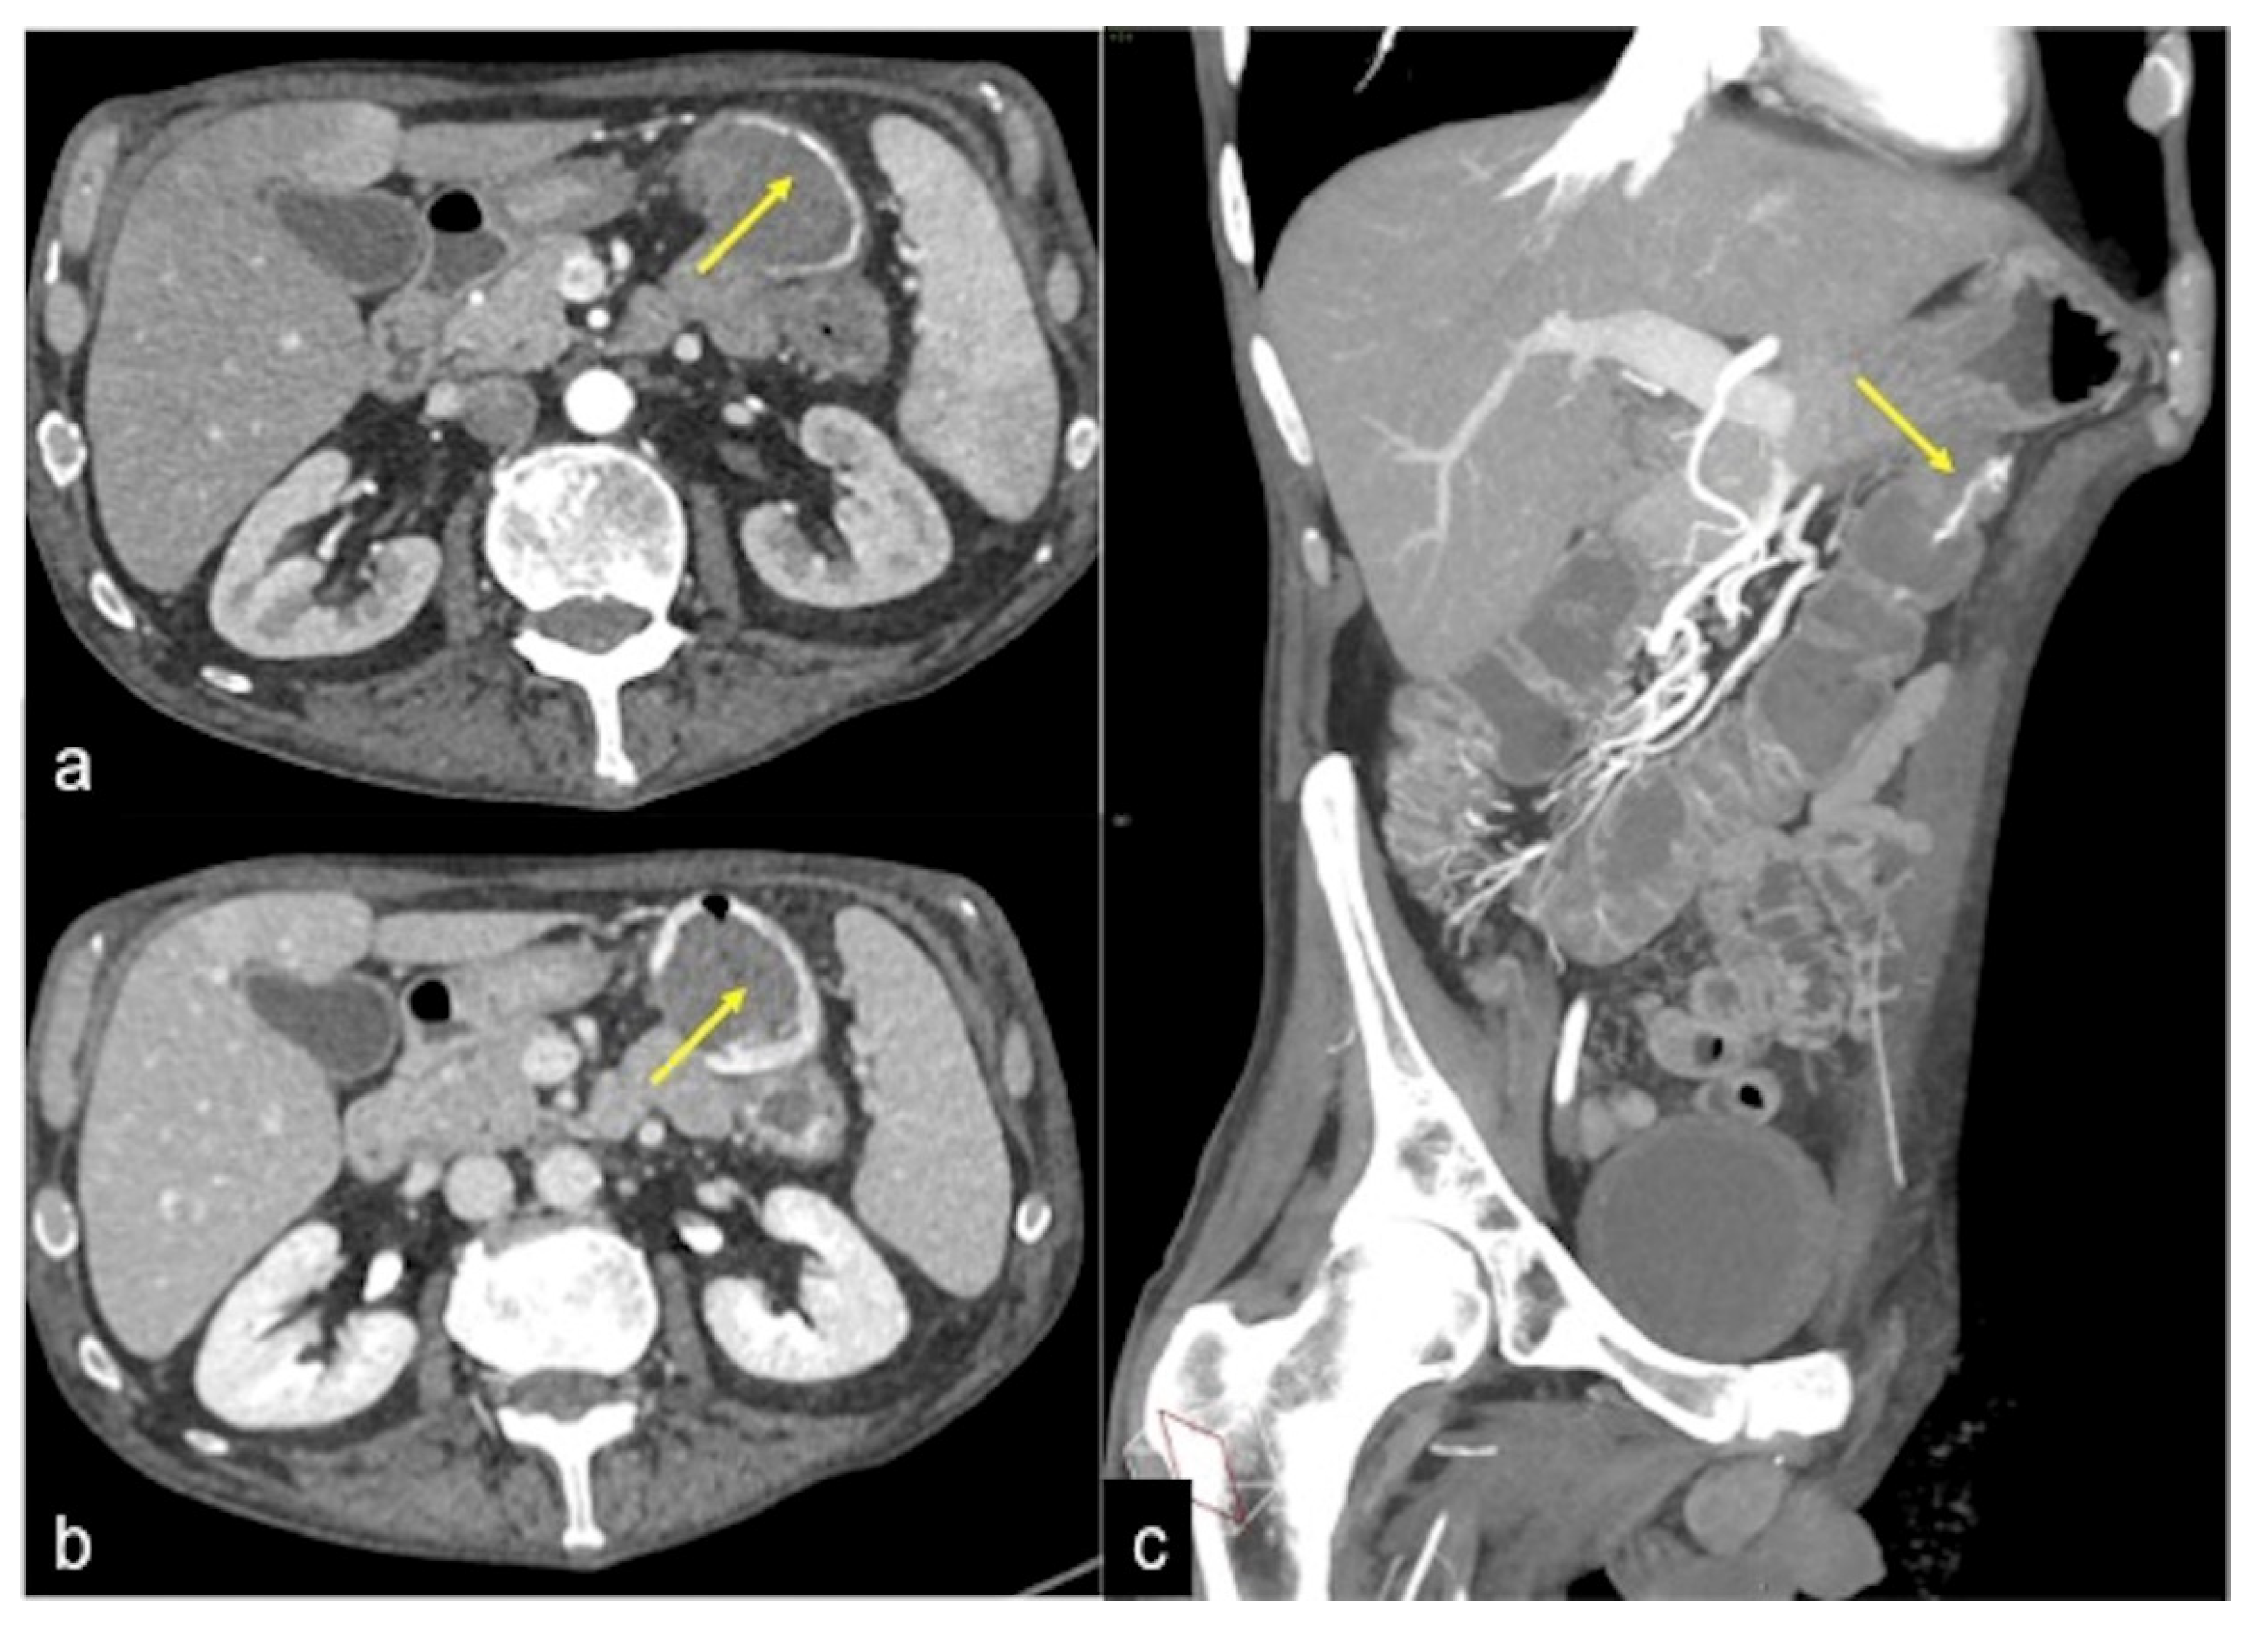

| Aorto-Enteric Fistula (Figure 31) | Bleeding in a patient with a history of surgery for aortic aneurysm. | A connection between the aorta and the intestinal lumen. Absence of adipose cleavage planes. |